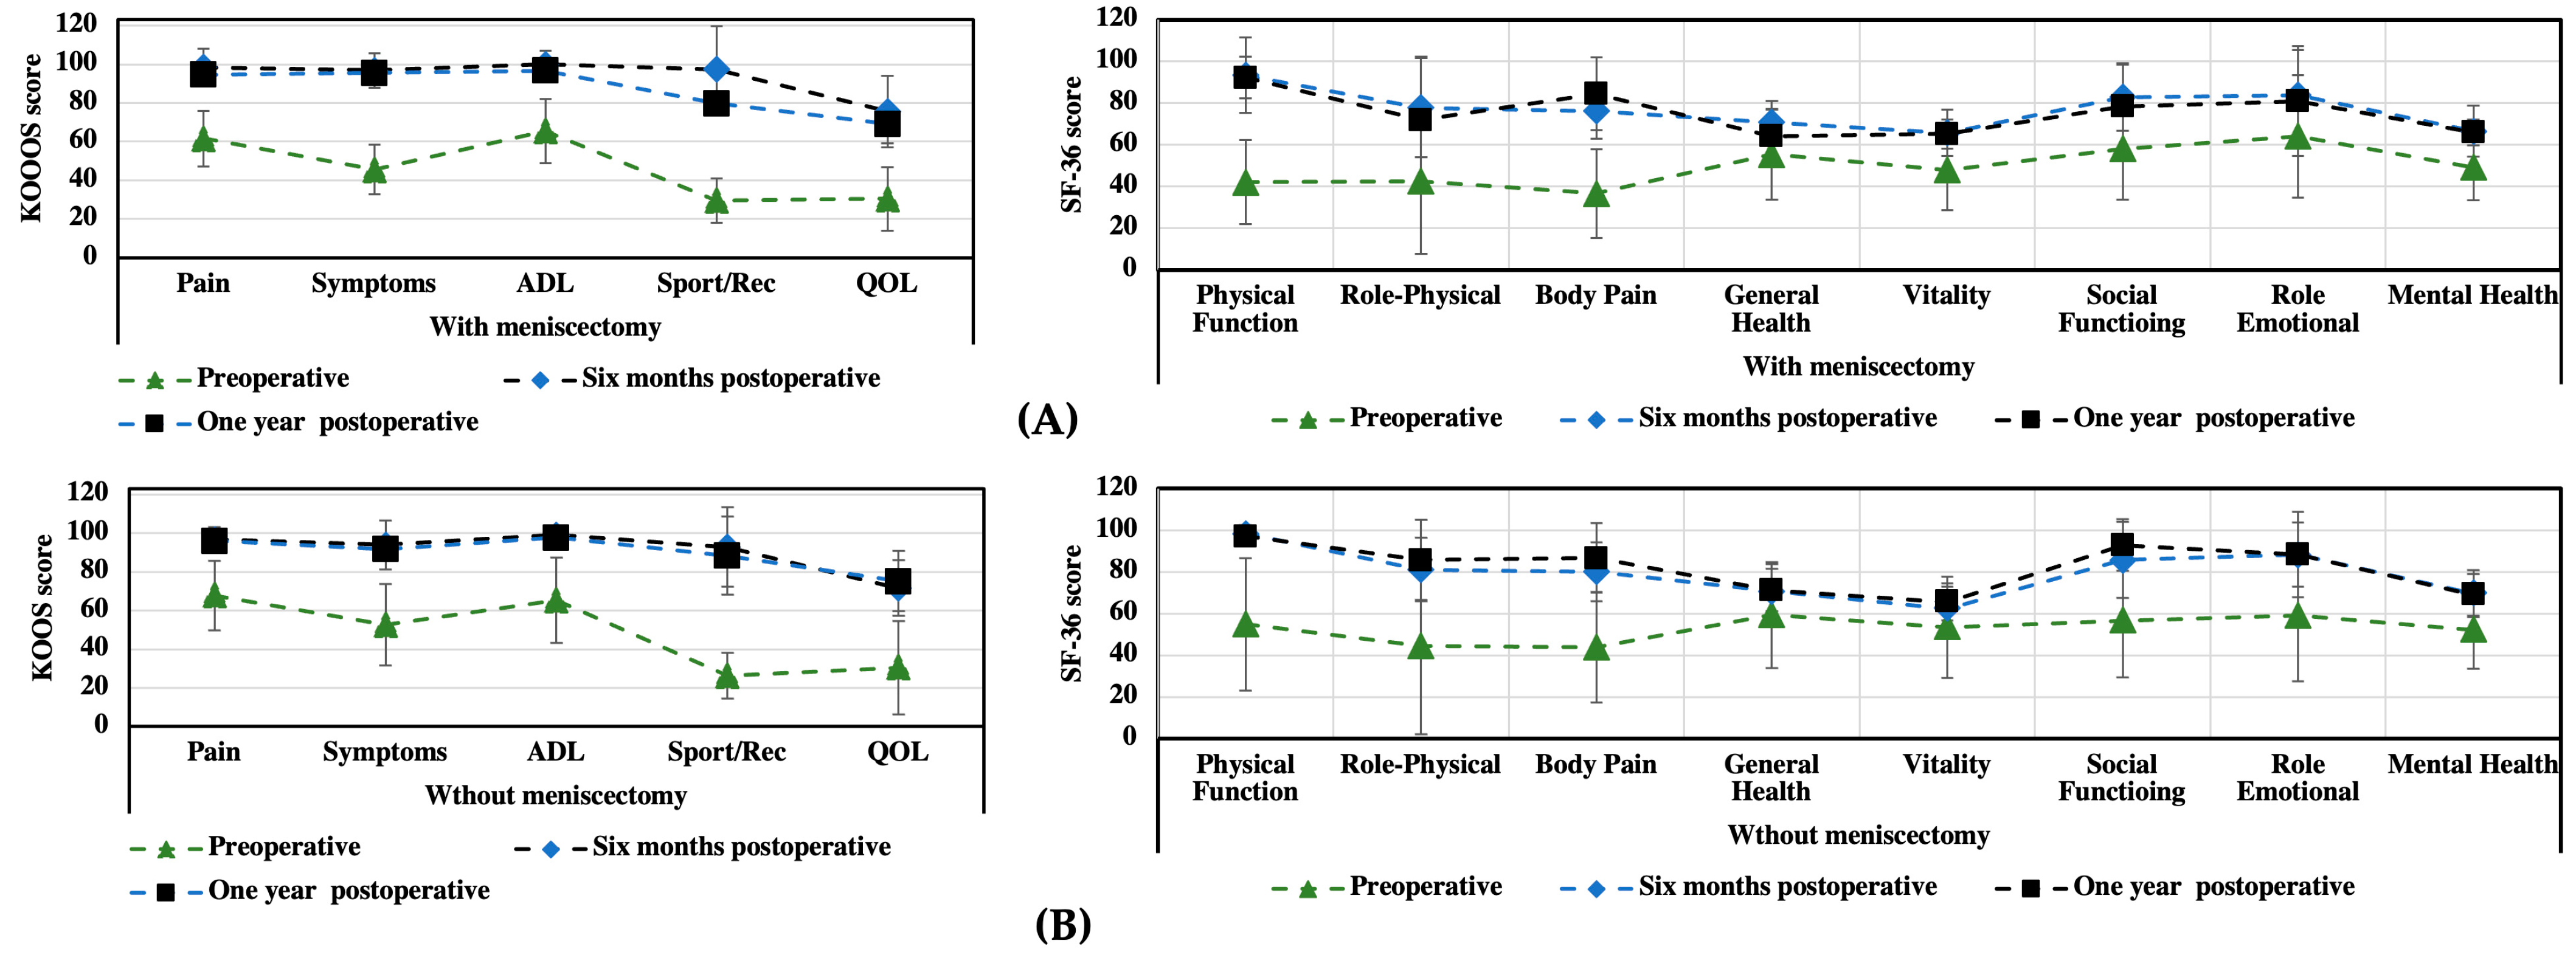

3.1. KOOS and SF-36 Scales

| Preoperative | Six Months Postoperative | One Year Postoperative | (before/after Six Months) | |

|---|---|---|---|---|

| KOOS | Mean ± SD | Mean ± SD | Mean ± SD | p |

| Patients (n) | 49 | 49 | 43 | |

| Pain intensity | 55 ± 18.2 | 96 ± 4.2 | 99.5 ± 2.3 | <0.05 |

| Symptoms | 46 ± 16.6 | 93 ± 6.5 | 98.2 ± 1.8 | <0.05 |

| Activities of daily living | 57 ± 25.5 | 99 ± 2.6 | 100 ± 0.0 | <0.05 |

| Sport/Rec | 14 ± 11.1 | 95 ± 7.7 | 99.8 ± 1.8 | <0.05 |

| Quality of life | 30 ± 18 | 76 ± 4.7 | 88 ± 8.8 | <0.05 |

| Preoperative | Six Months Postoperative | One Year Postoperative | ||

|---|---|---|---|---|

| SF-36 | Mean ± SD | Mean ± SD | Mean ± SD | (before/after Six Months) |

| Patients (n) | 49 | 49 | 43 | p |

| Physical function | 34 ± 18.5 | 95.6 ± 2.0 | 97 ± 2.5 | <0.05 |

| Role physical | 63 ± 46.5 | 76 ± 15.0 | 96 ± 3.7 | 0.345 |

| Bodily pain | 36 ± 18.7 | 78 ± 15,6 | 98 ± 2.3 | <0.05 |

| General health | 68 ± 17.1 | 70 ± 16.1 | 83 ± 15.8 | 0.401 |

| Vitality | 53 ± 20.6 | 64 ± 8.0 | 87 ± 7.1 | 0.067 |

| Social function | 64 ± 29.6 | 87 ± 13.6 | 90 ± 9.5 | 0.068 |

| Role emotional | 73 ± 42.0 | 83 ± 22.9 | 90 ± 13.3 | 0.285 |

| Mental health | 52 ± 9.8 | 68 ± 11 | 70 ± 10.8 | 0.464 |